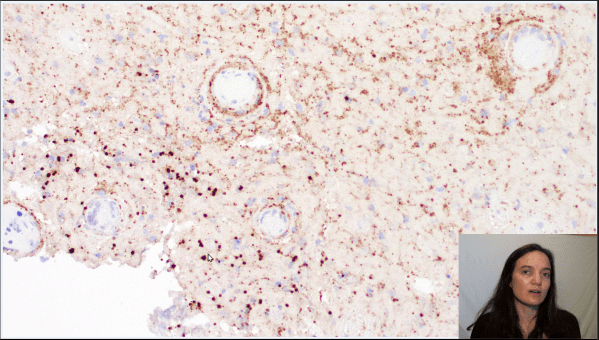

Video: Breast Cancer Metastasis to Brain

Join me for a narrated pathology review of breast cancer (ductal adenocarcinoma) metastatic to brain. https://youtu.be/EkRq-Vs5WoU